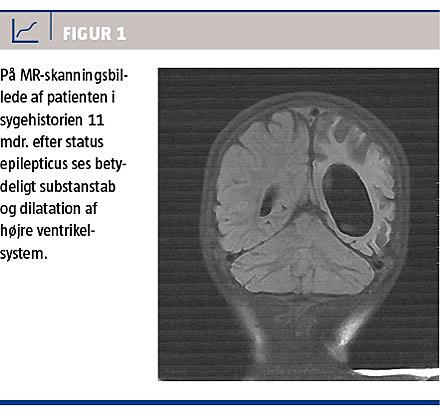

Ved opfølgning knap et år senere var hun ikke alderssvarende udviklet. Hun havde en højresidig parese med øget tonus, daglige epileptiske anfald og fremtrådte sprogligt og kognitivt som en toårig (biologisk alder knap fire år). En MR-skanning 11 måneder efter SE viste tilkommet betydeligt substanstab med let midtlinjeforskydning og dilatation af højre ventrikelsystem (Figur 1).